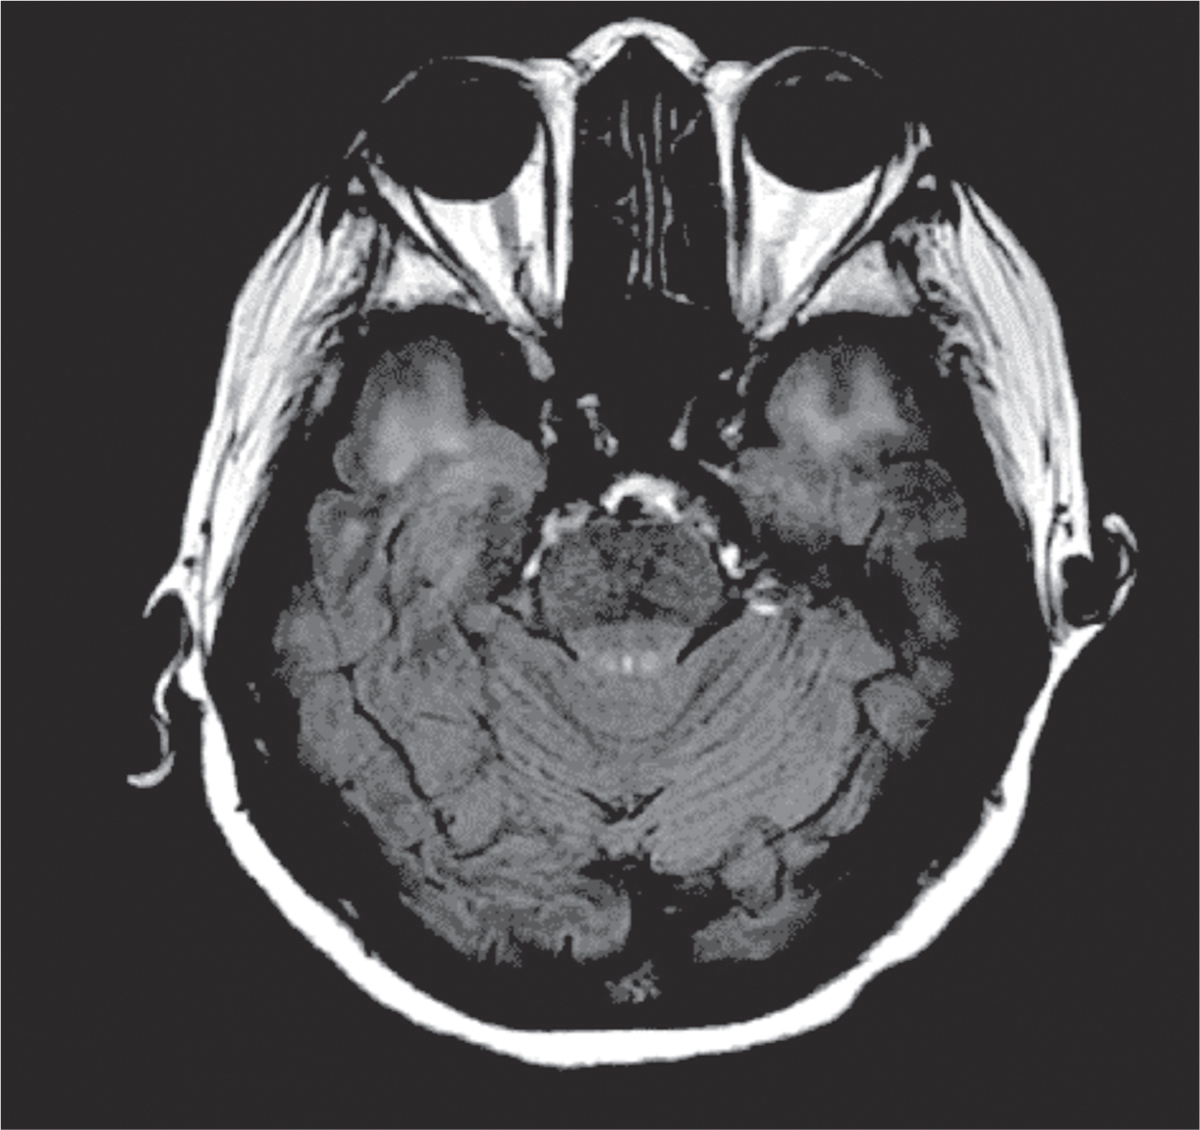

Figure 1.

IRM cérébrale en T2 FLAIR : hypersignaux de substance blanche confluents des deux pôles temporaux.